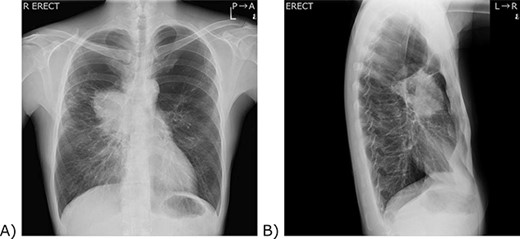

The patient was a male in his 40s. He visited an orthopaedic practitioner for multiple joint pain. No arthritis or rash was observed, but a tumour was detected on his chest X-ray, so he was referred to us (Fig. 1). He was a current smoker with a smoking index of 600. He did not have a past medical history other than chronic obstructive pulmonary disease. His mother suffered from lung cancer. He had an allergy to dairy products. A 9-cm irregular-shaped tumour was revealed in the hilum of the right lung by computed tomography (Fig. 2). The tumour seemed to invade the superior vena cava and azygos vein. Transbronchial biopsy was unsuccessful. The tumour was believed to be a non-small-cell lung cancer of clinical stage IIIB. As the tumour grew quickly, prompt surgery was scheduled.

Chest X-ray. (A) A frontal view. (B) A lateral view. (A) A 9 cm tumour was located in the right hilum of the patient. The right pulmonary artery and the lower part of the superior vena cava are silhouetted out, and the boundary cannot be seen. (B) The tumour was located anterior to the hilum of the lung.